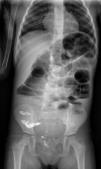

En radiografía abdominal se aprecian numerosos cuerpos extraños compatibles con semillas y dilatación de asas intestinales. El aspecto radiológico y la fotografía de las semillas expulsadas en heces, aportada por los padres, permiten identificar las semillas del cinamomo (Melia azedarach), árbol presente en el patio del colegio (fig. 1).

A) Radiografía de abdomen. Imágenes redondeadas hiperdensas en todo el marco cólico y en ampolla rectal compatibles con semillas ingeridas. B) Hojas y frutos de Melia azedarach, cinamomo o árbol del paraíso. Los frutos son drupas esféricas de 1cm de diámetro, de color verde, que torna a amarillo con su maduración.